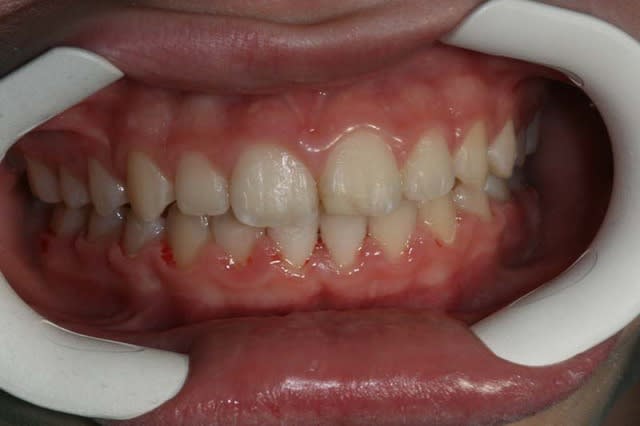

un cas traité sans bielles

suite,

j’obtiens le passage en Cl.I. avec seulement le reformage d’arcade, comme dans ce cas pris à la volée, (en cours de TTT).

J’ai traité ce cas avec un Q.H. en Sup., puis avec un MB. Inf., puis seulement un segmenté Sup. car le bas est Tjs. pl

us lent à réagir que le haut

on voit que l’arcade du bas est mieux reformée que l’arcade du haut

le prochain Rdv. est pour coller la fin du haut

un cas terminé que m'a sorti mon assistante

(sans bielles)